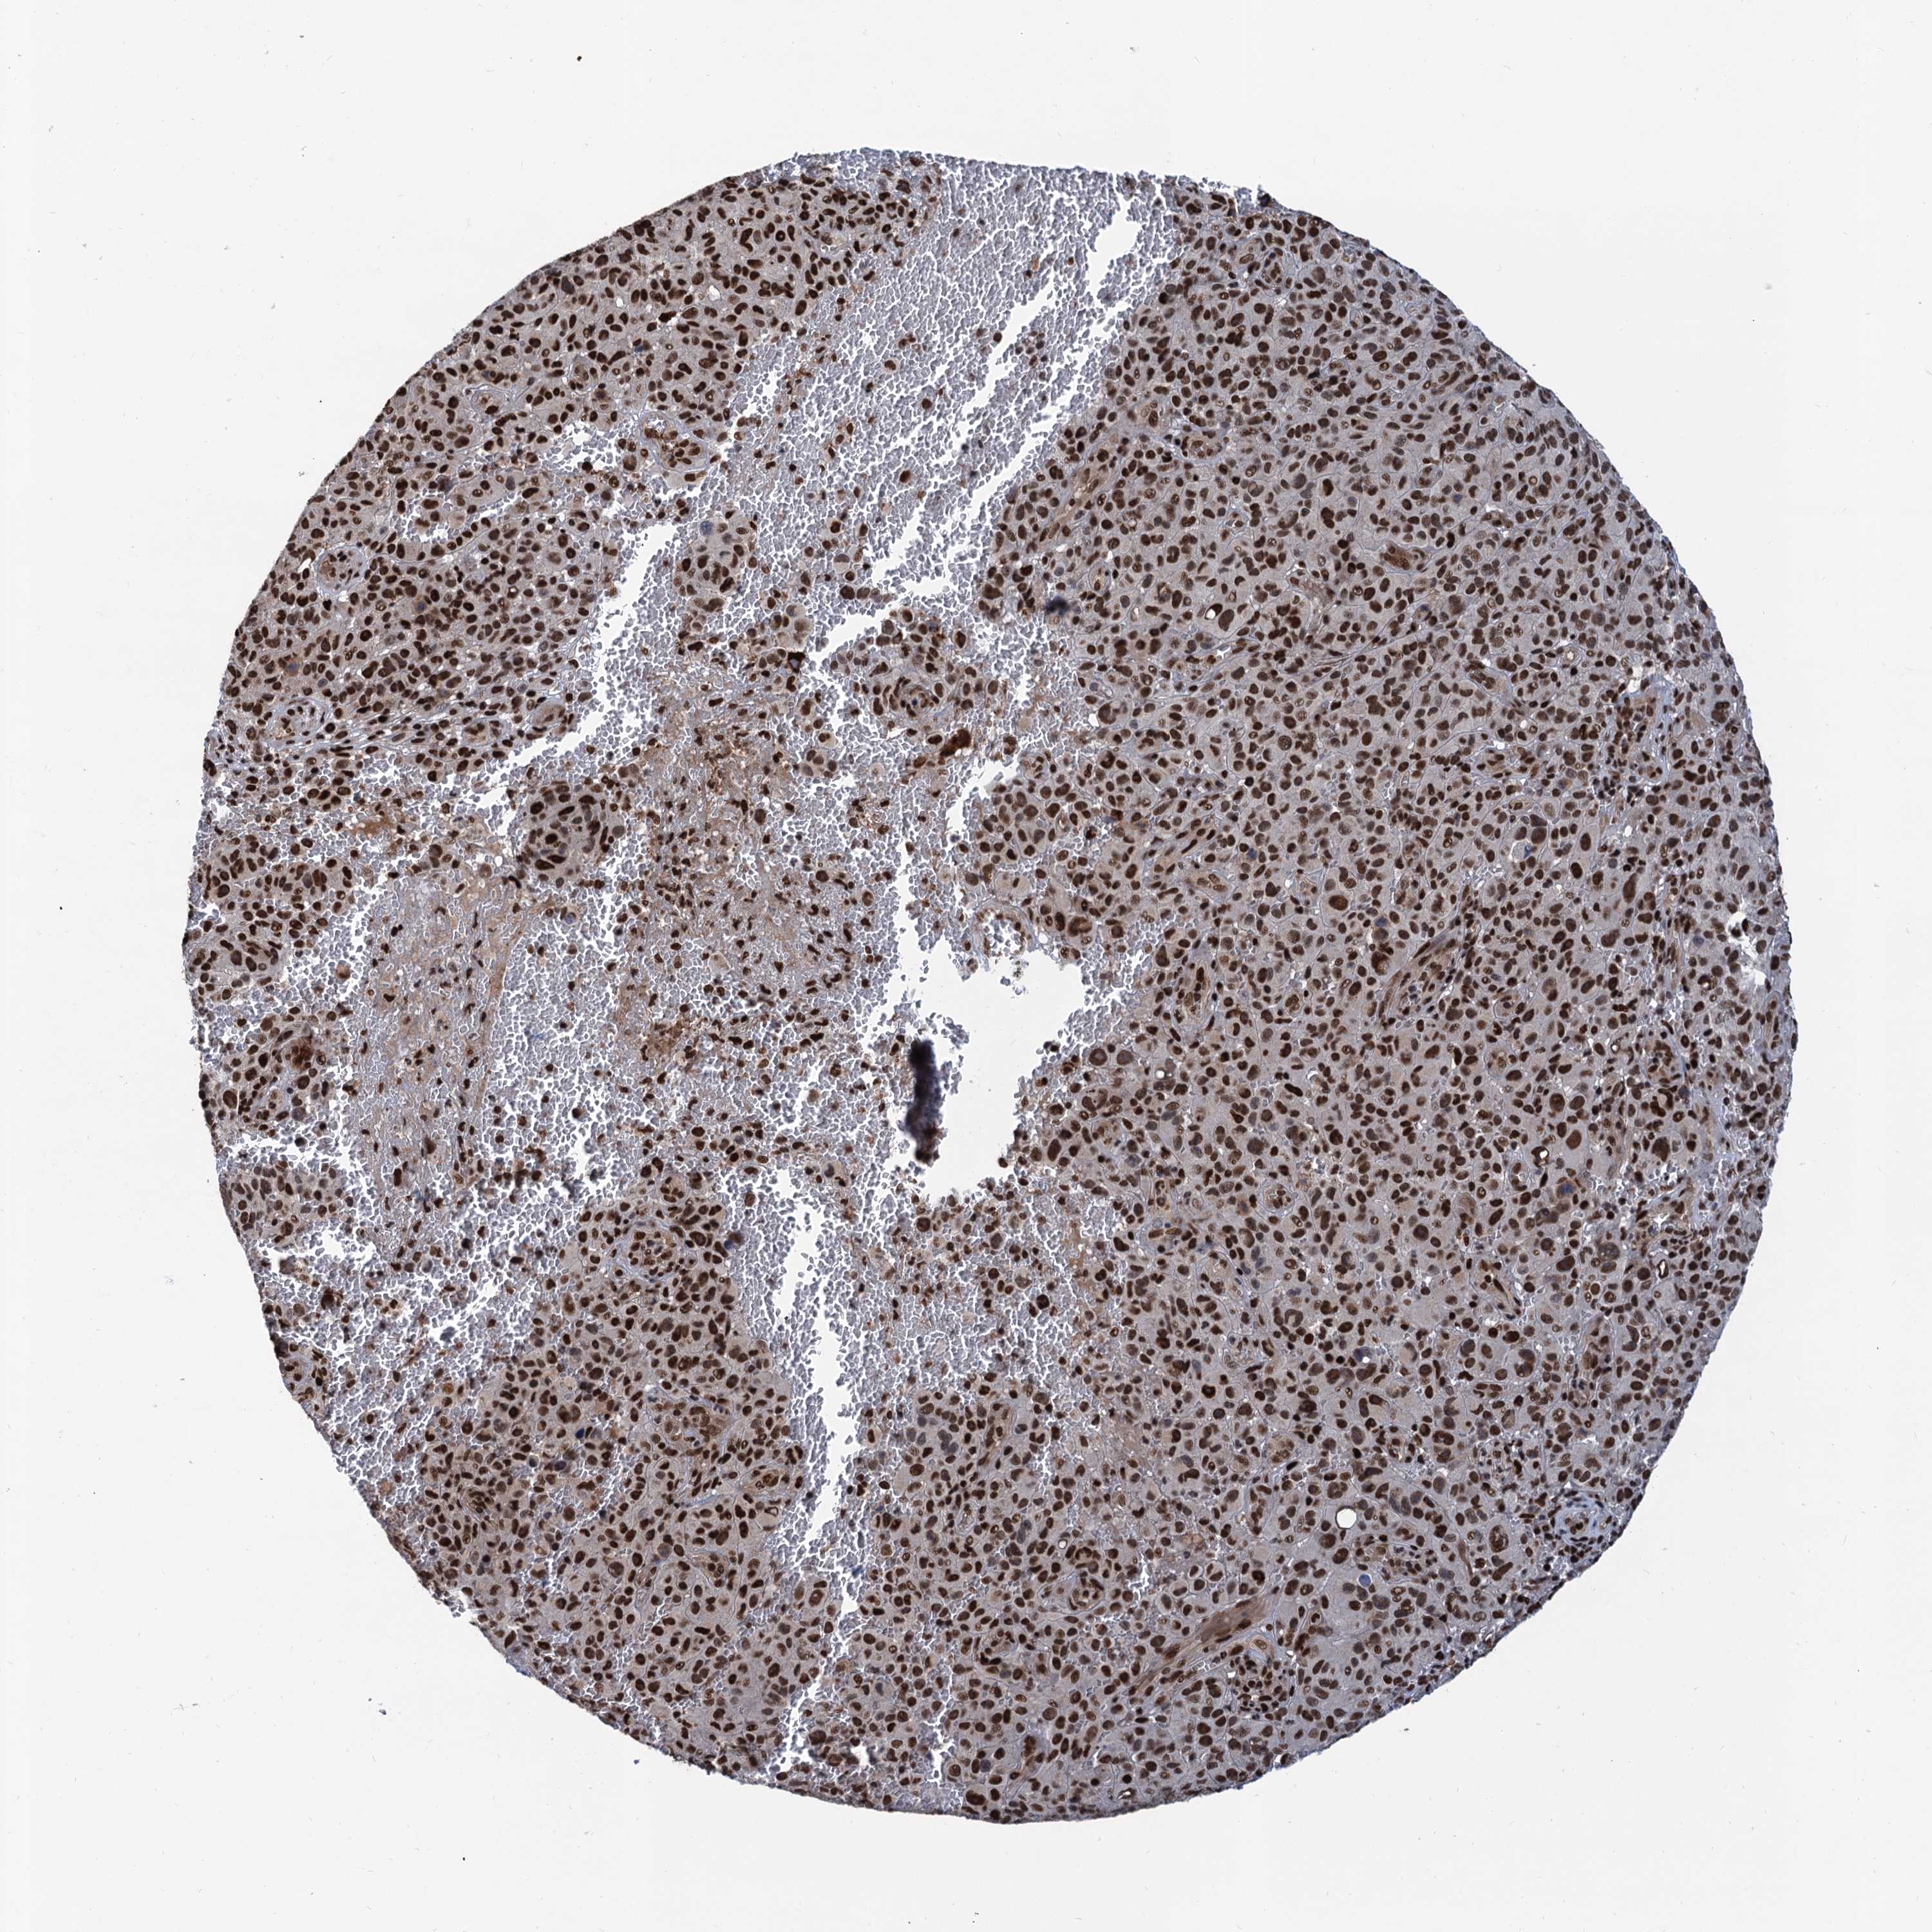

MELANOMA - Protein expressioni

A mouse-over function shows sample information and annotation data. Click on an image to view it in a full screen mode. Samples can be filtered based on level of antibody staining by selecting one or several of the following categories: high, medium, low and not detected. The assay and annotation is described here.

Note that samples used for immunohistochemistry by the Human Protein Atlas do not correspond to samples in the TCGA dataset.

Antibody stainingi

Antibody staining in the annotated cell types in the current human tissue is reported as not detected, low, medium, or high, based on conventional immunohistochemistry profiling in selected tissues. This score is based on the combination of the staining intensity and fraction of stained cells.

Each image is clickable and will lead to virtual microscopy that enables deeper exploration of all samples and also displays staining intensity scores, fraction scores and subcellular localization as well as patient and tissue information for each sample.

Antibody HPA040905

Antibody HPA041089

Staining

High

Medium

Low

Not detected

Intensity

Strong

Moderate

Weak

Negative

Quantity

>75%

75%-25%

<25%

None

Location

Nuclear

Cytoplasmic/membranous

Cytoplasmic/membranous,nuclear

Malignant melanoma, NOS

Malignant melanoma, Metastatic site